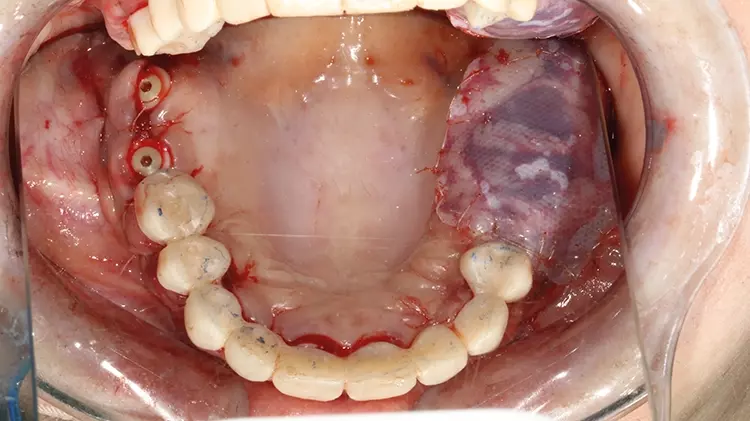

Abb. 13: Primärstabile, mittels schienenbasierter Navigation präzise inserierte SDS

Keramikimplantate im OK und UK in situ nach vollnavigierter Implantation mit

2ingis-Schienen. Alle einteiligen Implantate wurden direkt intraoperativ und intraoral

für die Langzeitprovisorien präpariert, die zweiteiligen wurden vorerst mit

einer Deckschraube verschlossen. SDS

Abb. 13: Primärstabile, mittels schienenbasierter Navigation präzise inserierte SDS Keramikimplantate im OK und UK in situ nach vollnavigierter Implantation mit 2ingis-Schienen. Alle einteiligen Implantate wurden direkt intraoperativ und intraoral für die Langzeitprovisorien präpariert, die zweiteiligen wurden vorerst mit einer Deckschraube verschlossen.

Die vollständige Sanierung mit den Keramikimplantaten SDS SWISS DENTAL SOLUTIONS wurde im vorliegenden Fall gemäß des SWISS BIOHEALTH ALL-IN-ONE CONCEPTS innerhalb einer Sitzung in Allgemeinnarkose durchgeführt (Abb. 13). Das für den Knochenstoffwechsel relevante Vitamin D kann nachweislich zusammen mit weiteren Mikronährstoffen, wie Vitamin K2, Magnesium etc., die Erfolgsquote der neutral, ohne Entzündungsprozess einheilenden Zirkonoxid-Keramik begünstigen [1-7]. Deshalb wurde zusätzlich zu weiteren vorbereitenden Maßnahmen im Rahmen eines operativen Begleitprotokolls (u.a. antibiotische Infusionen) auch der aktuelle Vitamin-D3-Wert erhoben, welcher nicht unter 70 ng/ml perioperativ liegen sollte [8].

Im Unterkiefer wurden nachfolgend nach gleicher Systematik erst die schienengeführte Spätimplantation vorgenommen, bevor die Sofortimplantationen im UKFZB folgten. Vereinzelte Knochenaufbaumaßnahmen erfolgten lediglich mit intraoralen Eigenknochen- sowie allogenen Spänen. In regio 33 erfolgte noch ein direkter Knochenaufbau mit einer aus regio 38 gewonnenen Knochenschale.

Um die Implantate wurden Eigenblutmembranen aus PRF (Platelet Rich Fibrin) eingelegt, um die Wundheilung zu fördern und zu beschleunigen [10-12]. Die Gingiva wurde anschließend atraumatisch um die Tissue-Level-Implantate mit den Knochenspänen und PRF-Matrices vernäht.